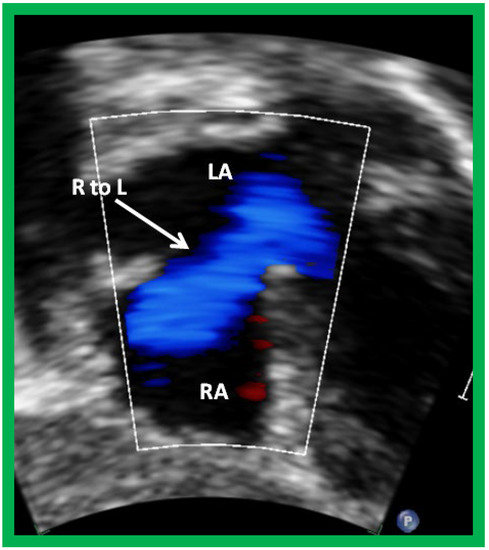

Following the demonstration of the atretic tricuspid valve, the sizes of the cardiac chambers are evaluated both by M-mode (Z scores) and 2D echocardiography; an enlarged RA, LA and LV and a small RV are seen (Figure 4, Figure 5 and Figure 6). Pulsed (not shown) and color Doppler (Figure 9) studies are helpful in illustrating right to left shunt across a PFO or an ASD.

Echo-Doppler studies should examine the adequacy of PFO/ASD to decompress the RA and allow unrestricted flow across it. In the majority of TA patients, the PFO/ASD remains wide open with unrestricted right to left shunt across it with laminar flow (Figure 18). This appears to be secondary to the persistence of fetal circulatory pathways. Only rarely does significant obstruction requiring intervention develop.

Figure 9. Selected video frame from subcostal view of a patient with tricuspid atresia demonstrating right to left (R to L) shunt (arrow) across the interatrial communication. LA, left atrium; RA, right atrium. Reproduced from Reference [29].